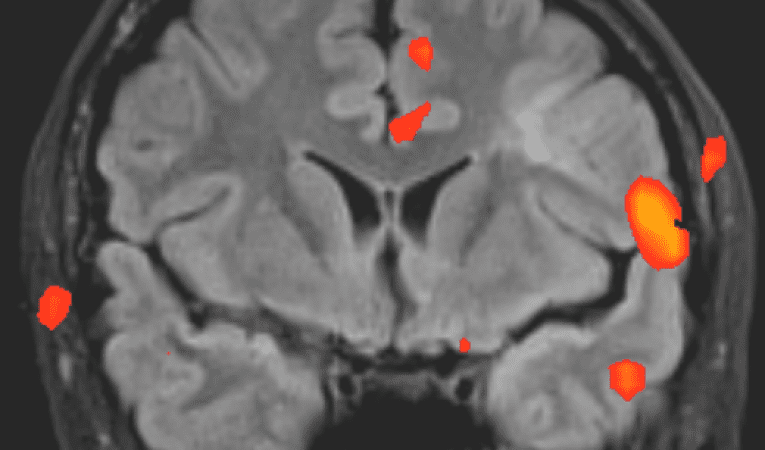

Prilikom obrade potrebno je napraviti magnetsku rezonancu mozga i vratne kralježnice. Okciptalnu neuralgiju moguće je liječiti antiepileticma tipa karbamazepina, okskarbamazepina ili pregabalinom.   U slučaju nedjelotbornosti moguće je učiniti blokadu okcipitalnog živaca pomoću anestetika i kortikosteroida. Potvrda dijagnoze je promtan gubitak boli koji može potrajati mjesecima. U novije vrijeme postoji radovi gdje se uspješnom pokazala aplikacija 50 jedinica botulinskog toksina u tom području.  U obzir dolaze i neurokirurške metode.